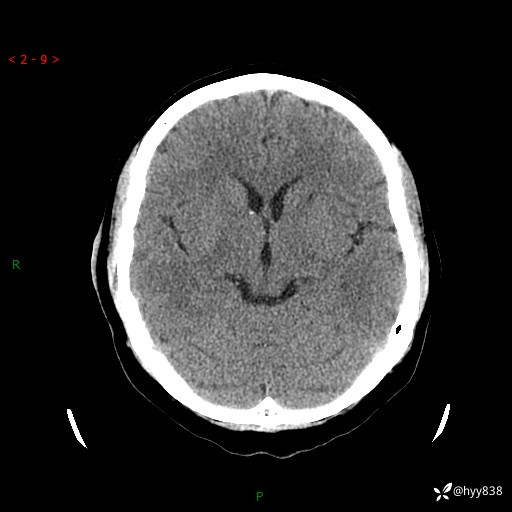

患者性别:男

患者年龄:28岁

简要病史:右肾肿瘤术后,常规复查

辅助检查:CT

临床诊断:右肾肿瘤术后

腹部CT+颅脑CT平扫